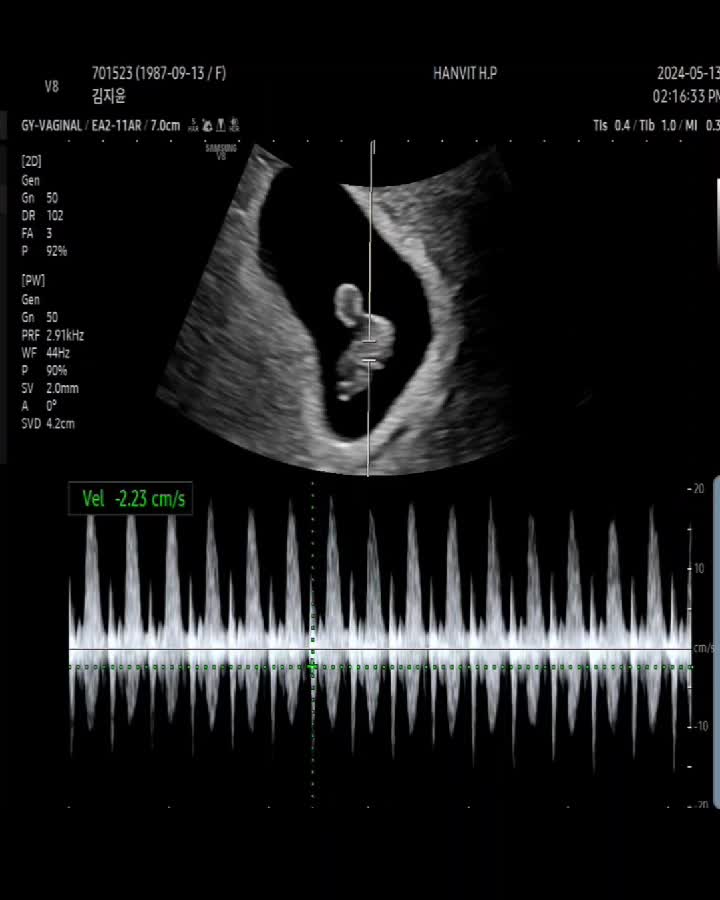

[19주차4일]정기검진/벌써 아기얼굴을 볼 수있다니!/신기해♥

19주차 정기검진 - 벌써, 아기얼굴을 볼 수 있구나♥ 드디어 한달을 기다린 정기검진날! 안산 한빛여성병원...